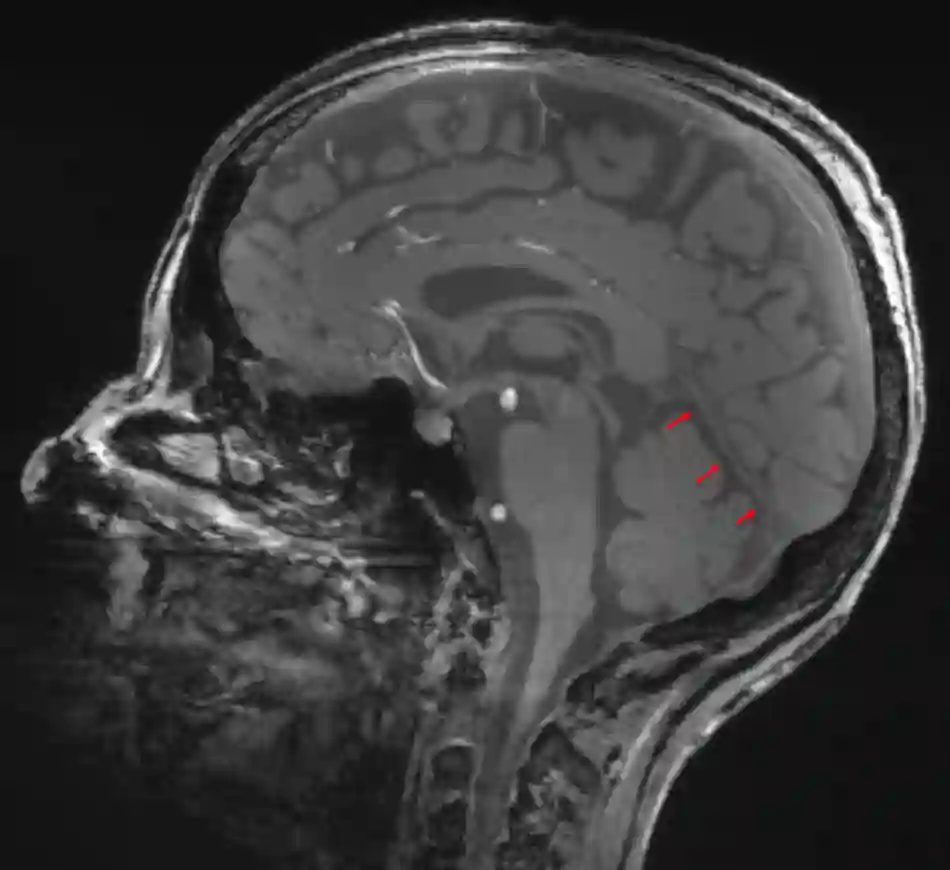

Tentorium cerebelli im sagittalen MRT

Das Tentorium cerebelli im Anschnitt auf einem sagittalen MRT Bild.